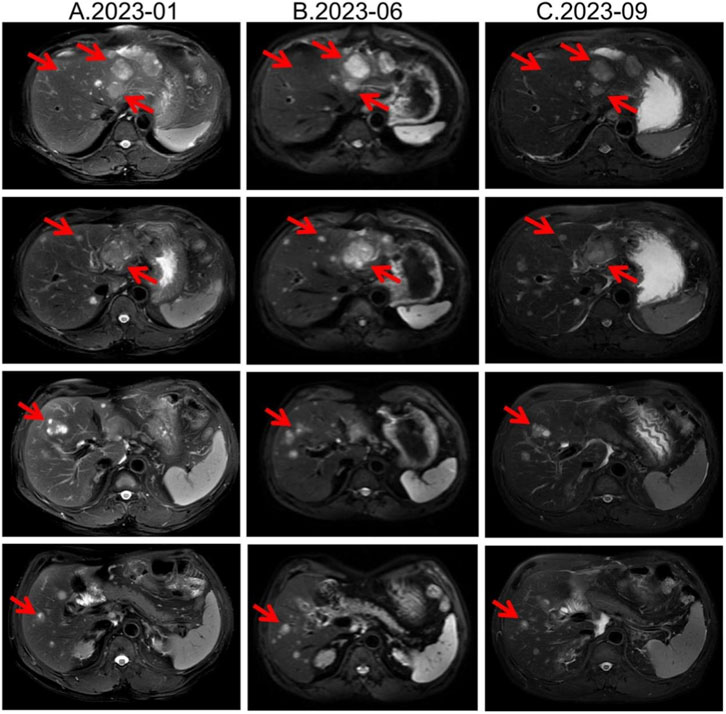

Second-line therapy began in September 2022, with surufatinib 300 mg daily. In the SANET III phase III trial, surufatinib significantly prolonged PFS in pNETs (Xu et al., 2020). The MRI efficacy evaluations in January, June, and September 2023 all demonstrated SD (Figure 2). During treatment he developed mild-to-moderate proteinuria and anemia (hemoglobin 78 g/L). Considering the patient experienced intermittent melena in September 2023, after MDT discussion and temporary drug discontinuations he was screened for the “[177Lu]Lu-DOTATATE Injection versus Long-Acting Octreotide Study”. [68Ga]Ga-DOTATATE imaging demonstrated that some hepatic metastases were SSTR-negative, and he therefore failed screening (Figure 3). Surufatinib was resumed at a reduced dose of 200 mg daily. On 8 January 2024, the patient passed approximately 200 mL of dark red stool. A gastroscopy revealed multiple small-intestinal ulcers at the gastroenteric anastomosis site (A1 stage, Forrest III). After a comprehensive evaluation of efficacy and safety, surufatinib was discontinued.

CT and PET scan images comparing liver lesions from September 2023 (left) and February 2025 (right). The scans show increased intensity and size of lesions in 2025, highlighted by red circles. The liver lesion SUVmax increased from 18.76 to 83.08, and SUVmean from 7.5 to 44.49, indicating progression post-everolimus treatment.

Figure 3. Changes in [68Ga]Ga-DOTATATE uptake were noted before and after everolimus, with a representative liver lesion highlighted by a red circle on both PET/CT panels. A small inset table summarizes its SUVmax and SUVmean values pre- and post-treatment. (A) 2023-09 [68Ga]Ga-DOTATATE PET/CT, Intravenous injection of [68Ga]Ga-DOTATATE (4.15 mCi), with whole-body imaging performed at approximately 60 min post-injection. Multiple slightly low-density shadows were seen in the liver parenchyma, and no Ga68 DOTATATE uptake was observed in some lesions within the liver. No increased uptake signals were observed in the abdominal and pelvic cavities. (B) 2025-02 [68Ga]Ga-DOTATATE PET/CT. Intravenous injection of [68Ga]Ga-DOTATATE, 3.13 mCi, followed by whole-body PET/CT imaging at approximately 60 min post-injection. Multiple liver metastases, with a significant increase in Ga68 DOTATATE uptake level compared to 2023-09 PET/CT (SUVmax:83.08). No increased uptake signals were observed in the abdominal and pelvic cavities.

The MDT recommended repeating [68Ga]Ga-DOTATATE imaging to reassess tumor burden and SSTR2 expression. On 12 February 2025, [68Ga]Ga-DOTATATE uptake in multiple hepatic metastases was markedly increased, indicating SSTR2 upregulation following everolimus therapy (Figure 3; Supplementary Tables S1, S2). The patient was then re-screened for the “[177Lu]Lu-DOTATATE Injection versus Long-Acting Octreotide Study” and was randomized to the control arm, receiving 60 mg of long-acting octreotide every 4 weeks, and a CT performed in May 2025 showed SD on response assessment (Supplementary Figures S1, S2).

Notably, this patient exhibited dynamic changes in SSTR expression during everolimus treatment. Pre-treatment [68Ga]Ga-DOTATATE imaging showed negligible uptake, indicating low SSTR expression often seen in poorly differentiated or highly proliferative NETs (Kim et al., 2024). After several months of everolimus, hepatic lesions regained high SSTR expression and “lit up” on imaging—a phenomenon of SSA receptor re-expression that has gained attention (Mileva et al., 2021).

Quantitatively, although SUV_max values of 10–40 are common in well-differentiated NETs, outliers with very high uptake have been reported on [^68Ga]Ga-DOTATATE PET/CT (tumor SUV_max up to 118), so the value of 83.08 observed here falls within published extremes (Kayani et al., 2009). Our two studies were acquired on the same system with ∼60-min uptake times and similar activities, consistent with current SNMMI/EANM procedure standards; thus, protocol differences are unlikely to explain the increase (Hope et al., 2023). The marked rise is more plausibly attributed to high post-treatment SSTR2 availability and favorable background activity (with normal spleen and liver SUVs in the expected ranges), as reflected by elevated tumor-to-liver and tumor-to-spleen ratios now detailed in Supplementary Tables S1, S2.